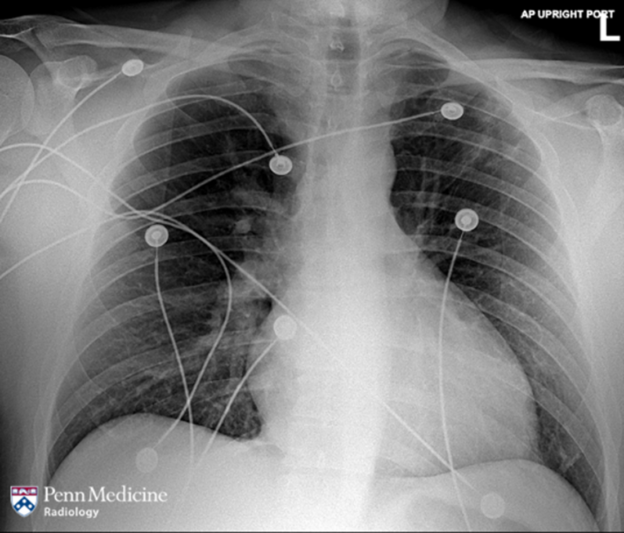

50-year-old man with progressive worsening dyspnea